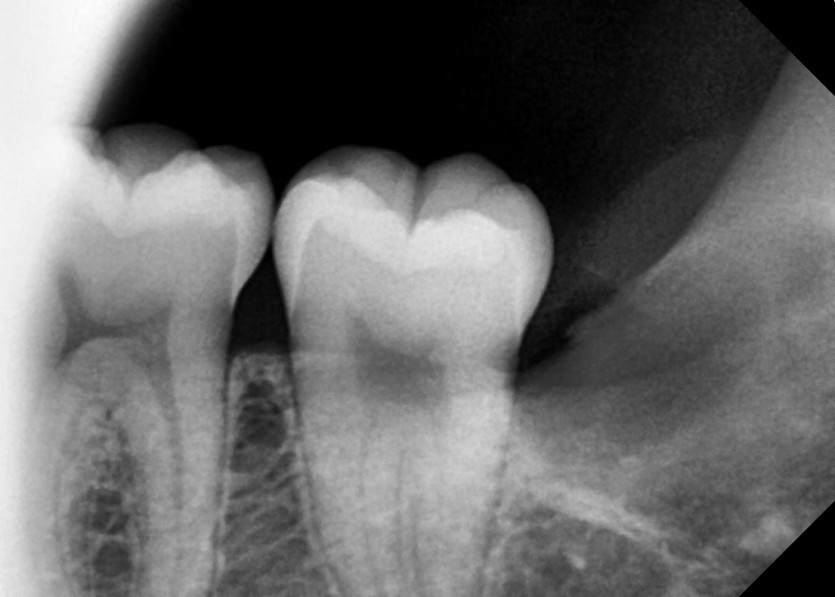

#28,38 사랑니 발치

구강 외과 전문의가 당일 발치했습니다.